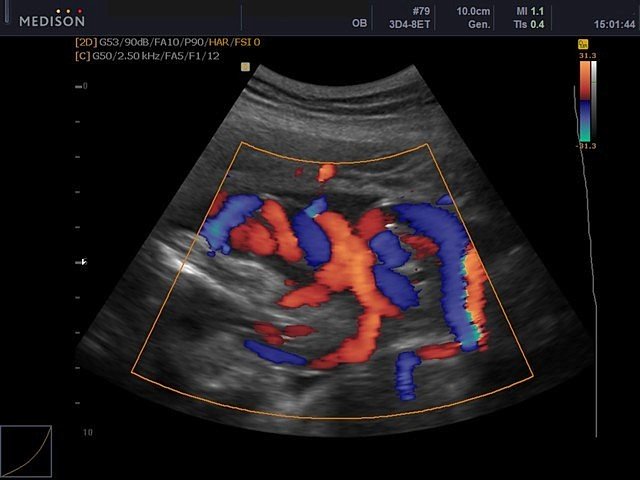

Umbilical cord, color doppler

Umbilical cord, color doppler (echogramm №432)

[RU] Ultrasound image №432: Umbilical cord in color doppler mode.